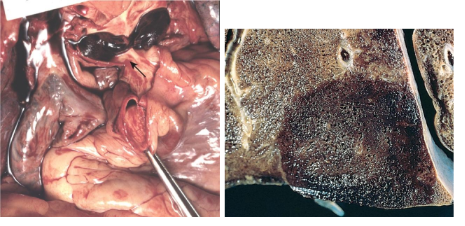

A

TEP